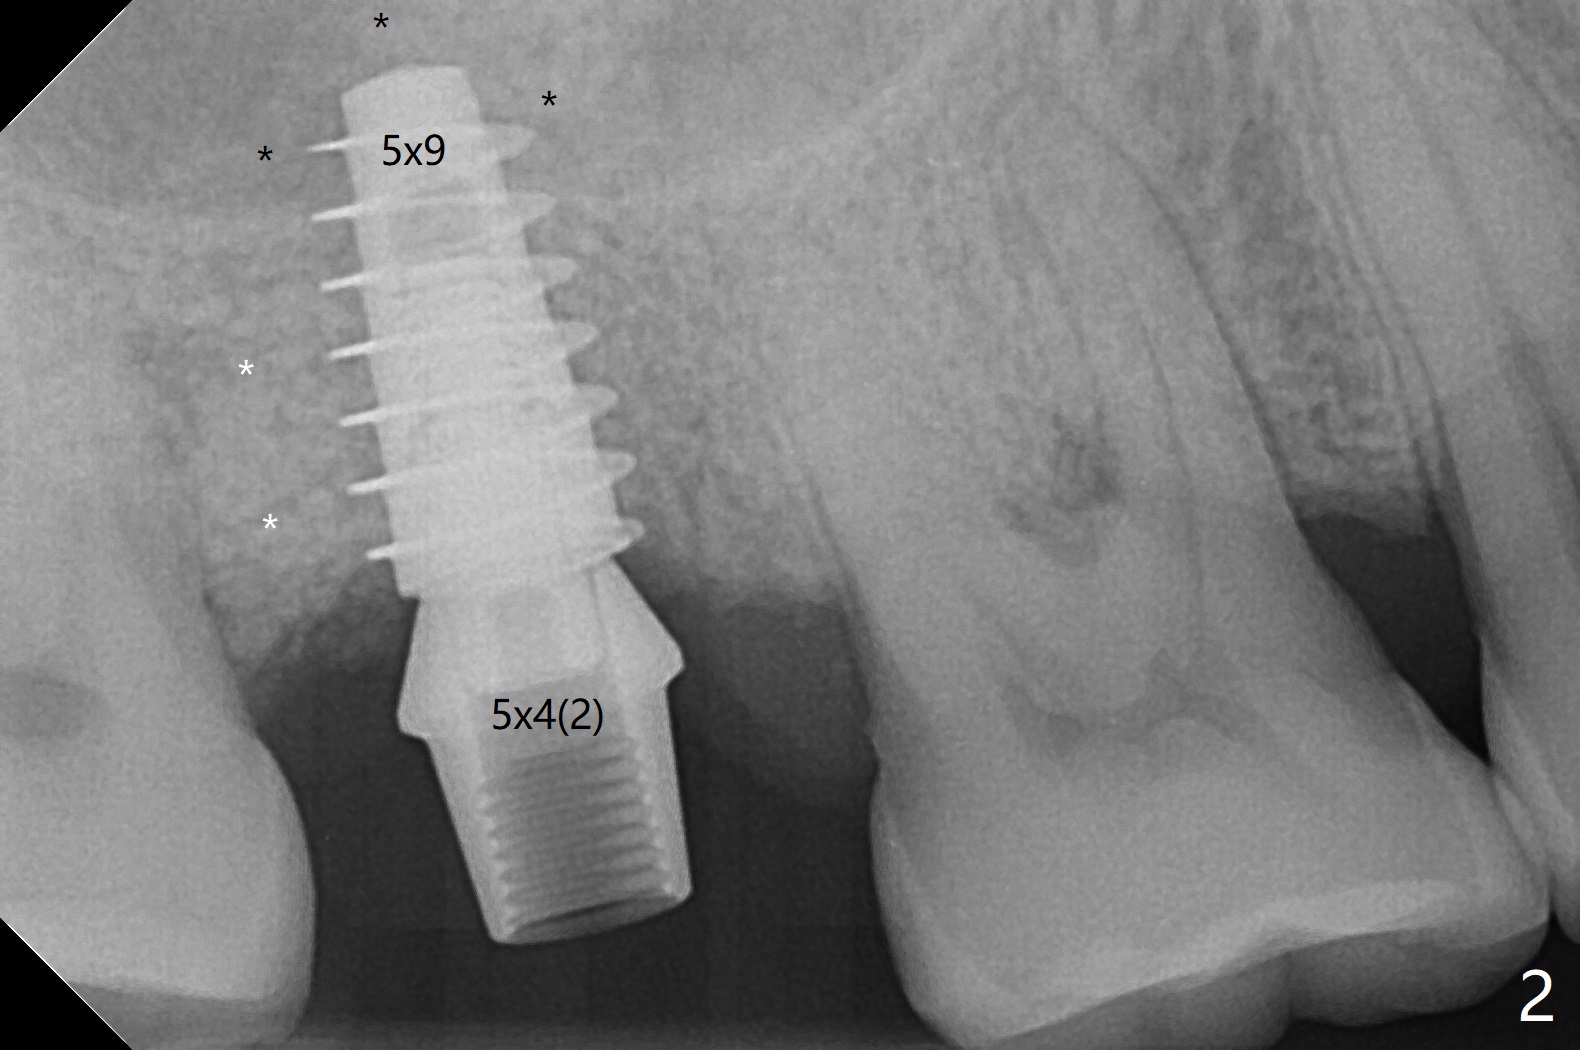

The tooth #2 has severe distobucal (DB) infection before and after extraction (Fig.1 *); sinus lift is done with 4.5x11 mm dummy implant using guide. After placing bone graft into the sinus and the osteotomy (Fig.2 black *), a 5x9 mm implant is placed with >30 Ncm. Second round of bone graft is placed around the implant, including DB defect (white *). Then a 5x4(2) mm pair abutment is placed, followed by the third round of bone graft (Fig.3 *). Finally an immediate provisional is fabricated to keep the graft in place. The implant is loose nearly 4 months postop.